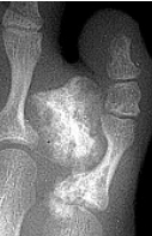

| Describe what is occurring at the head of the 3rd met | Freiberg’s infarction (avascular necrosis of the metatarsal head) |